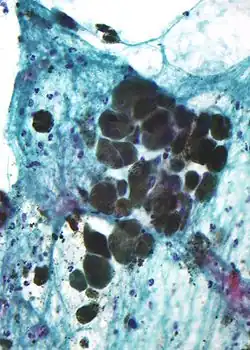

Micrograph of melanin pigment (light refracting granular material—center of image) in a pigmented melanoma

Melanin is brown, non-refractile, and finely granular with individual granules having a diameter of less than 800 nanometers. This differentiates melanin from common blood breakdown pigments, which are larger, chunky, and refractile, and range in color from green to yellow or red-brown. In heavily pigmented lesions, dense aggregates of melanin can obscure histologic detail. A dilute solution of potassium permanganate is an effective melanin bleach.[53]